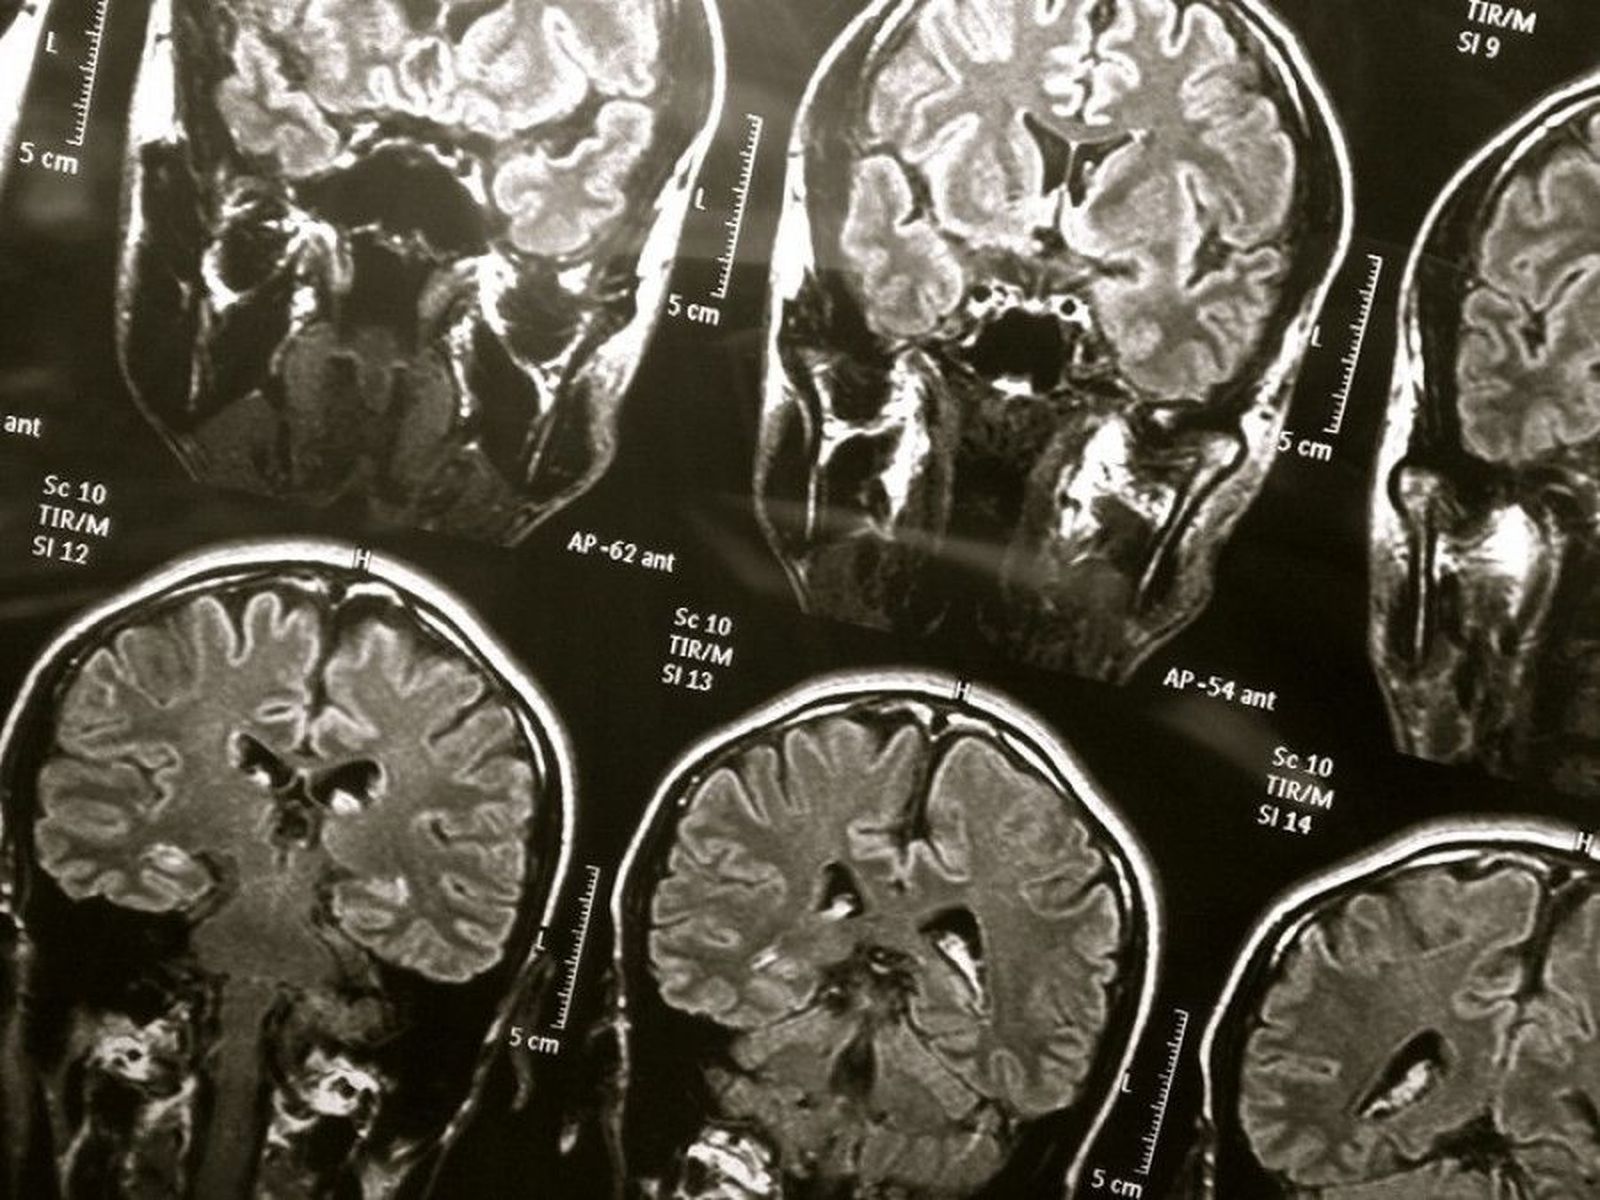

Día nacional del daño cerebral adquirido: Te puede pasar a ti, nos puede pasar a cualquiera

Este sábado se celebra en toda España el Día Nacional del Daño Cerebral.

“Te puede pasar a ti, nos puede pasar a cualquiera”, este es el lema del Día Nacional del Daño Cerebral que se celebra este sábado en todos los puntos de España. Con este día, las asociaciones quieren tener presente a las más de 100.000 personas que, como cada año en nuestro país, se han tenido que enfrentar a cambios radicales de su proyecto de vida causados principalmente por ictus, una de las causas más comunes de discapacidad en las sociedades desarrolladas, un traumatismo craneoencefálico provocado por fuerte impacto en el cerebro a consecuencia de un accidente laboral o de tráfico, un tumor cerebral u otras lesiones que les causan Daño Cerebral Adquirido (DCA) y hacen que su vida y la de su familia cambie, radicalmente, en cuestión de segundos.